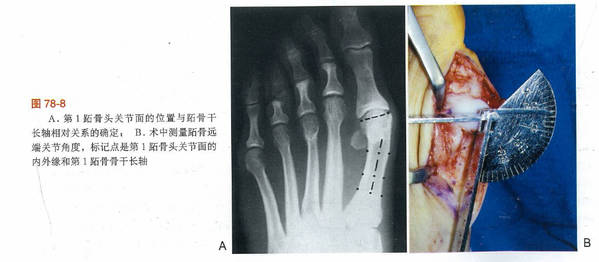

拇外翻的病因:

遗传、性别、生活习惯、关节疾病等因素

拇外翻病理改变:

病变发生在第一跖趾关节

第一跖骨内翻,跖骨头向内移位,而籽骨在拇收肌、拇短屈肌和跖横韧带等结构的牵拉下维持原位,籽骨相对于跖骨头向外发生移动,跖骨头跖侧骨嵴被磨平籽骨失去了跖趾关节在屈伸中的滑车作用,籽骨的外移将会牵拉拇趾近节趾骨发生旋转。

其他两个涉及第一跖趾关节的解剖学改变也可以引起拇外翻

第一个改变为跖骨头关节面偏斜,其偏斜的角度被称为跖骨远端关节固角(DMAA)

第二个改变为趾近节趾骨基底的关节角相对于其纵轴出现偏斜,其偏斜角度被称为趾骨近端关节固角(PAA)